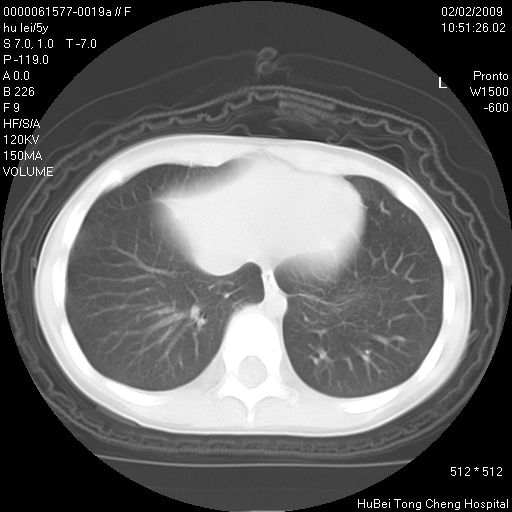

标题: PED1732:M5Y,右肺囊性占位!

患者:男,5。无明显不适,拍胸片考虑右肺囊肿。

行ct扫描,图象如下: